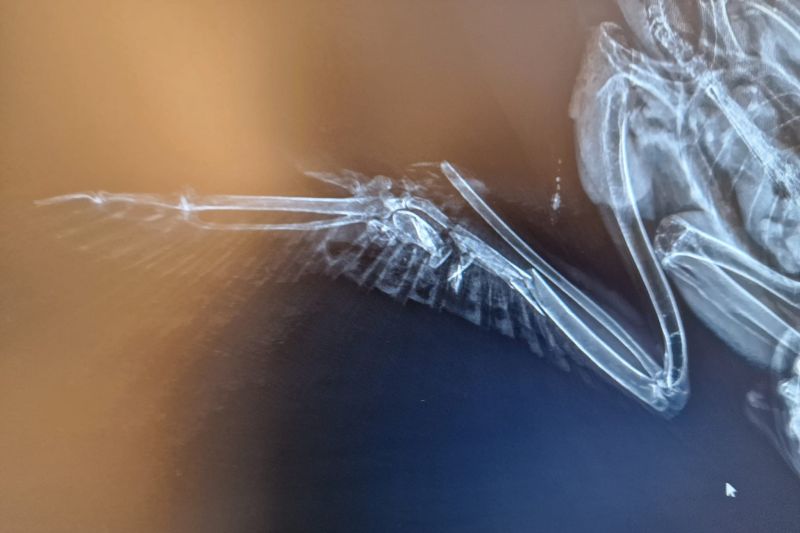

In unserer modernen, verbauten Welt ist der Luftraum kein sicherer Ort mehr. Was für uns Fortschritt und Infrastruktur bedeutet, wird für Eulen, Greif- und Wasservögel oft zur tödlichen Falle. Eine Wildvogelstation ist weit mehr als nur ein Ort für die Aufzucht flauschiger Küken – sie ist ein Lazarett an der vordersten Front.

Die Verletzungen, die wir täglich behandeln, sind keine Unfälle der Natur. Sie sind die direkten Folgen unseres menschlichen Wirkens:

• Infrastruktur-Opfer: Anflüge gegen Hochspannungsleitungen und die rotierenden Schaufeln von Windrädern sorgen für schwerste Traumata und Amputationen

• Tödliche Barrieren: Stacheldraht zerschneidet Schwingen; Glasfronten und der Straßenverkehr führen zu massiven inneren Verletzungen und Knochenbrüchen.

Die folgenden Bilder zeigen ungeschönt den Alltag in der medizinischen Notversorgung. Sie sehen Blut, offene Wunden und chirurgische Eingriffe. Das ist die notwendige, harte Arbeit hinter den Kulissen. Wir kämpfen um jedes Leben – mit Skalpell, Verband und fachmedizinischer Expertise –, um die Fehler wiedergutzumachen, die unsere Zivilisation verursacht hat.

Die folgenden Aufnahmen sind nichts für schwache Nerven. Sie zeigen Blut, offene Frakturen und den harten Kampf im Operationssaal. Wir zeigen sie bewusst. Denn diese Bilder sind die ungeschönte Antwort auf unsere Art zu leben.

Hinter jedem Foto steht ein Schicksal, ein Kampf und unser unermüdlicher Einsatz, das Unrecht der Zivilisation medizinisch zu korrigieren.